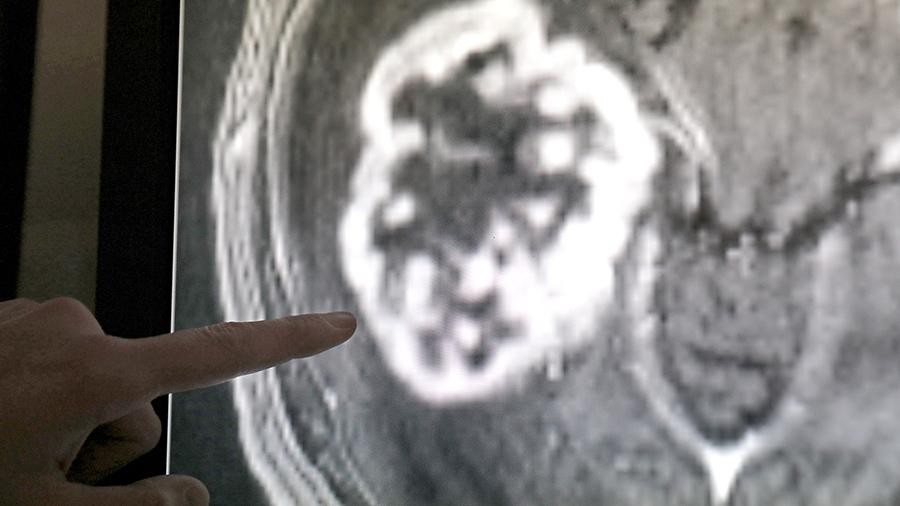

— Нам удалось соединить фотосенсибилизатор бактериохлорин с наночастицами магнетита, которые являются одновременно доставщиком лекарства и контрастным агентом, — рассказал «Известиям» другой автор работы, заведующий лабораторией «Биомедицинские наноматериалы» НИТУ «МИСиС» Максим Абакумов. — Мы получили новый инструмент, позволяющий с помощью МРТ эффективно отслеживать накопления активных молекул в пораженном органе, что обеспечивает нужную концентрацию и максимально сжатые сроки хирургического вмешательства.

Она отметила, что накопление магнитных частиц в опухоли позволит ее очень точно локализовать, что представляет собой отдельный результат научной работы, весьма важный для лечебной практики.